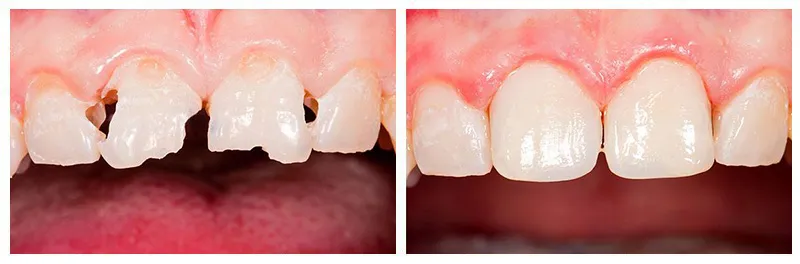

Case Studies

Welcome to our Case Studies! Here, you’ll discover examples from just a few of the thousands of patients we’ve had the pleasure of helping enhance their smiles and improve their quality of life. All of the case studies feature real patients and their actual results.

At Alpha Dental Excellence, we welcome you just as you are. No matter your smile’s current state, we’re here to support you on your journey to better dental health. After assessing your needs, we’ll craft a personalized plan to give you the confident, radiant smile you deserve